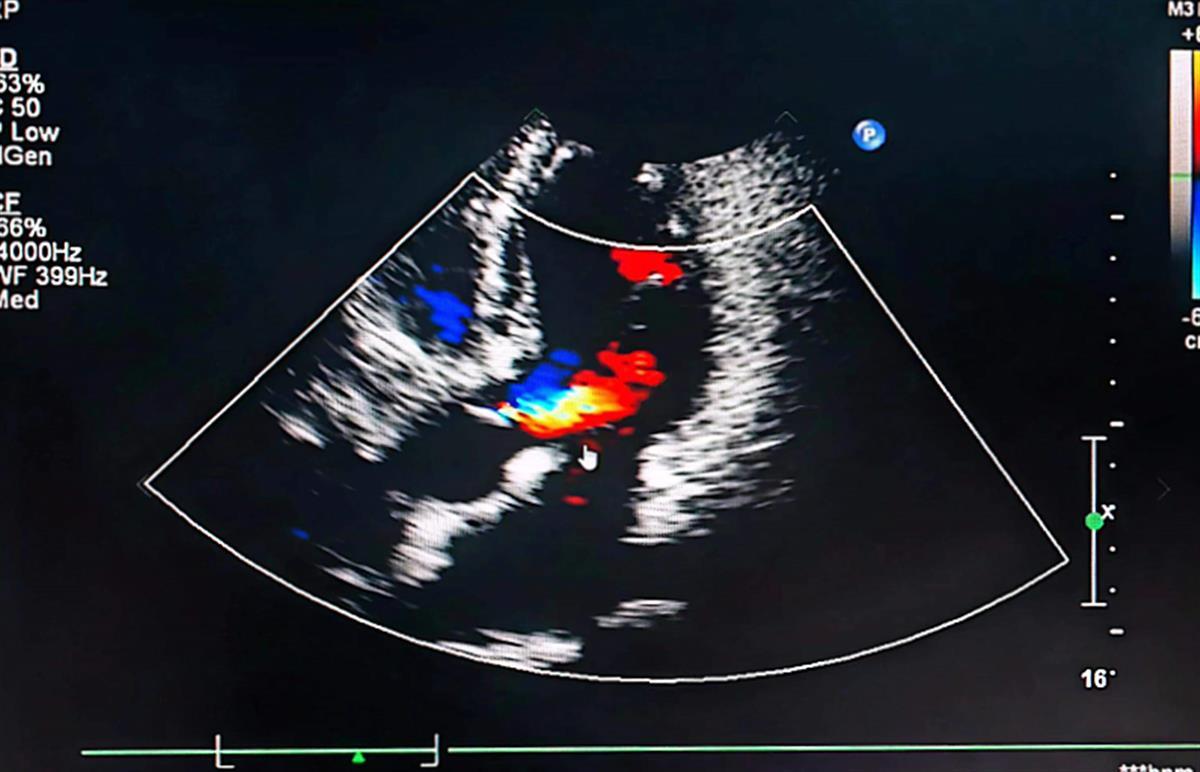

彩超结果显示李先生主动脉瓣重度关闭不全(通讯员供图)在武汉市第四医院古田院区,心血管内科主治医师李磊接诊后对李先生进行了详细检查。李磊医生检查后发现,虽然李先生描述的症状类似心绞痛,但他并没有“三高”、抽烟饮酒等冠心病高危因素,心电图也没有发现明显的心肌缺血征兆。在听诊中,李磊发现患者主动脉瓣有明显的杂音,建议李先生去做彩超。检查中医生发现患者出现主动脉瓣二瓣化、主动脉瓣重度关闭不全,反复胸闷的罪魁祸首找到了。